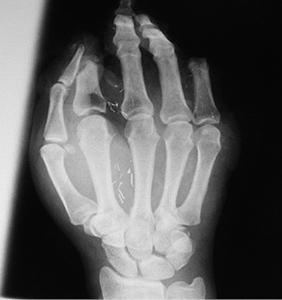

Vėliau pacientė dar keletą kartų hospitalizuota į stacionarą, jai atlikta odos „Z“ plastika tarpupirščiuose dėl susiformavusių traukiančių randų. Praėjus 13 m. po laisvojo įnervuoto lopo transplantacijos, pacientė pakviesta įvertinti rekonstruotos plaštakos, pirštų jautrumo ir funkcionalumo. Pirštų jautrumas buvo vertinamas naudojant dviejų taškų diskriminacijos testą. Vertintas statinis (švelnus bakstelėjimas sensitometro adatėlėmis į odos paviršių) ir dinaminis (švelnus braukimas sensitometro adatėlėmis per odos paviršių) pirštų jautrumas, fiksuojant greitai ir lėtai į sudirginimą reaguojančius receptorius. Pacientės prašyta atsakyti, kokiu mažiausiu atstumu ji jaučia dirginimą kaip du taškus, o ne kaip vieną. Nustatyta, jog tiek statinio, tiek dinaminio jautrumo dažniausia riba buvo 13–15 mm. Plaštakos funkcionalumui įvertinti pacientės paprašyta paimti rašiklį, parodyti, kaip rašo. Įvertinta ir nufotografuota lopo donorinė vieta.

Atokieji rezultatai, praėjus maždaug 13 m. po rekonstrukcinių operacijų. Pacientės taip pat paprašyta parodyti, kaip sugeba suimti rašiklį. Nufotografuota donorinė dešinės pėdos vieta (13–15 pav.)